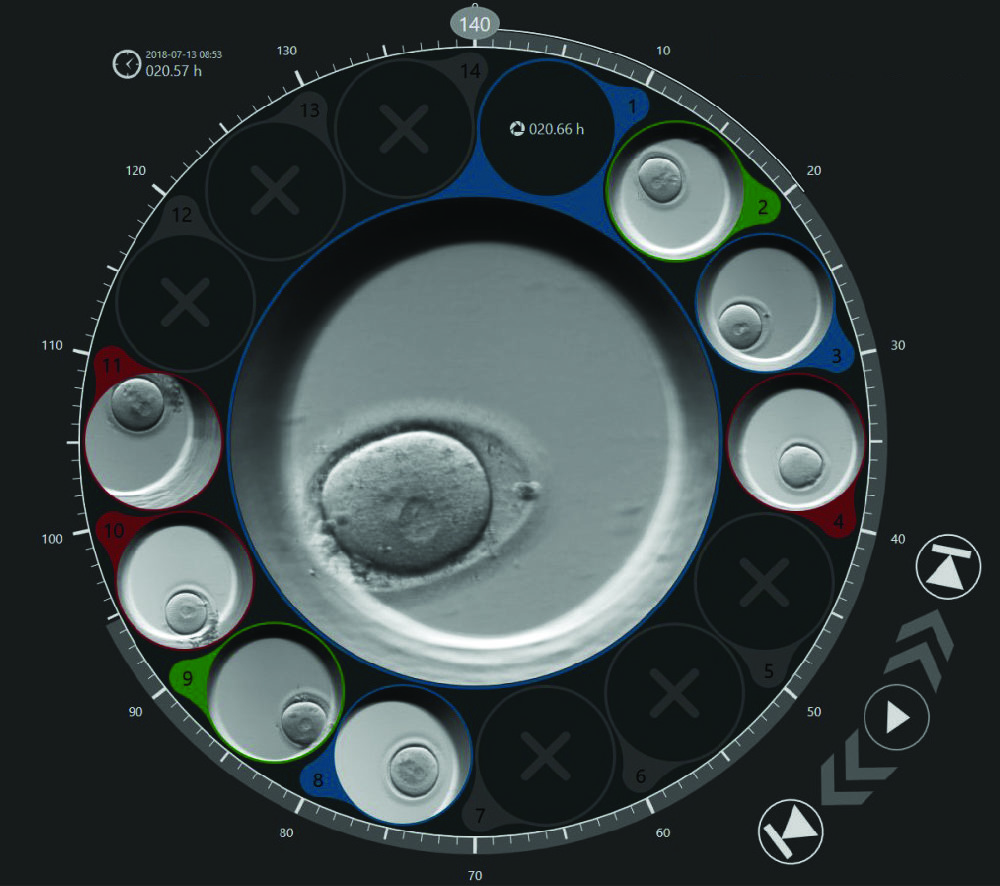

- Time-Lapse — это специальный инкубатор с встроенной микрокамерой, который:

- Искусственный интеллект оценивает каждый этап развития

- Эмбрион развивается в стабильных условиях, без стресса и внешнего вмешательства.